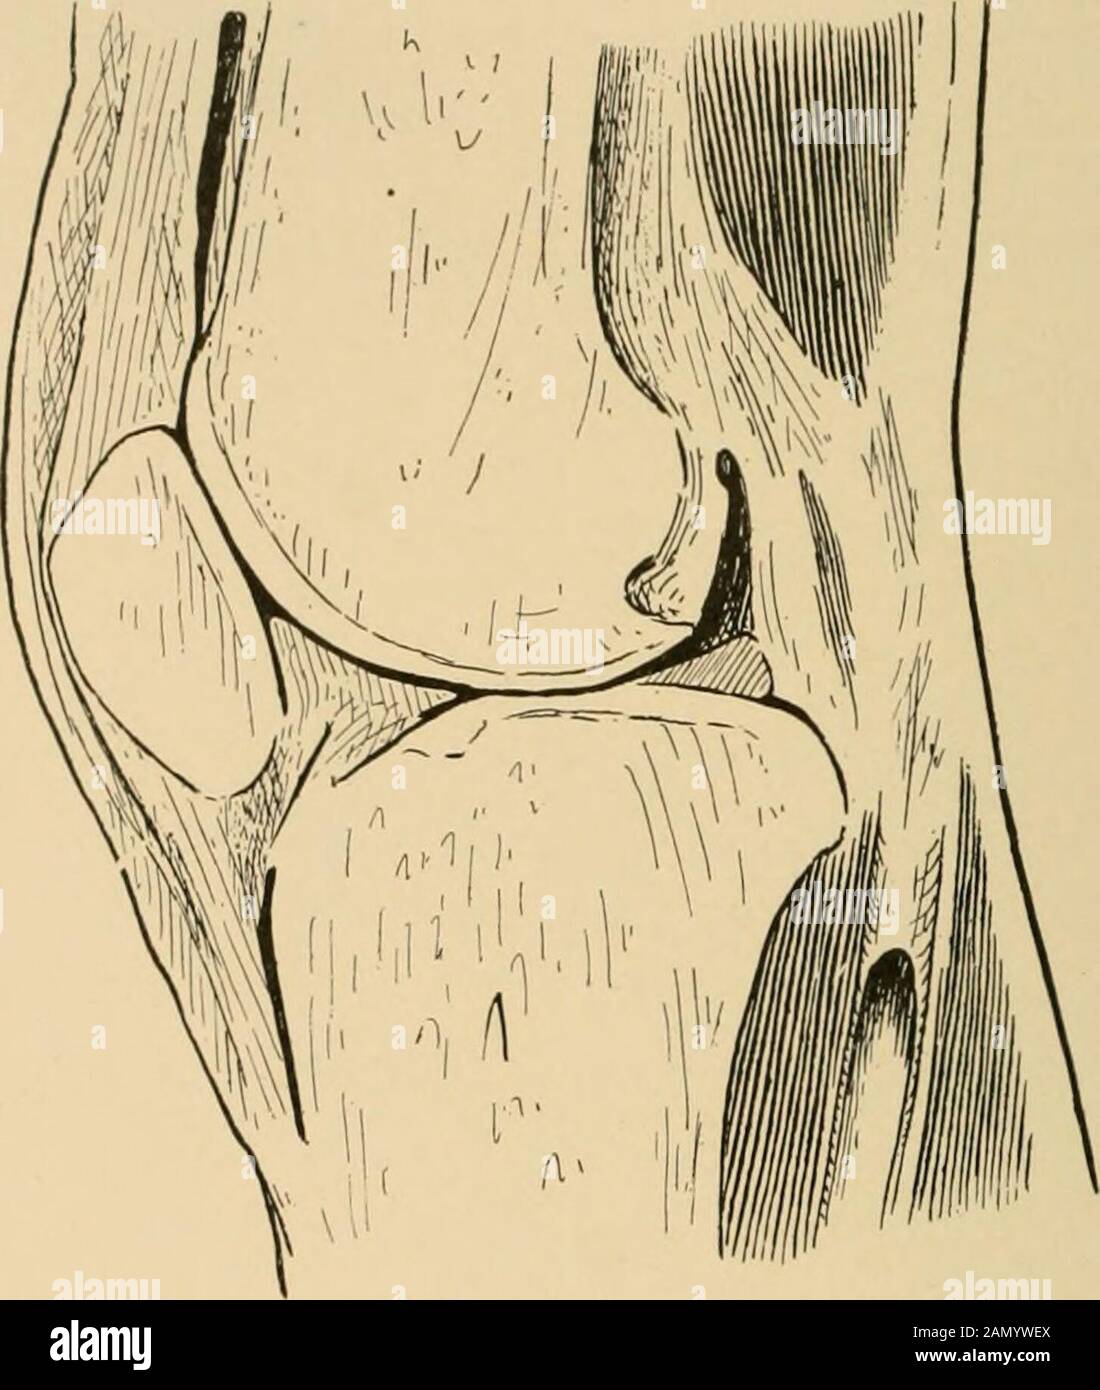

Le traitement des fractures . Fig. 444.—la section horizontale gelée de l'articulation du genou, montrant l'étendue latérale de la synovialmembrane (le professeur Dwights spécimen). La bordure supérieure est le tendon du muscle extenseur quadriceps. De chaque côté de l'os sont attachés respectivement à l'immenmus interims andvastatus externus. Sous les insertions de la vastiis une partie de la faible fixation de la lata de fascia de la cuisse. 3*9 320 FRACTURES DE LA ROTULE À la bordure inférieure de la rotule est le tendon patellaire. Thistendon est inséré dans le tubercle du tibia, et c'est sepa-. Fig. 445.—Anteroposterio Banque D'Imageshttps://www.alamyimages.fr/image-license-details/?v=1https://www.alamyimages.fr/le-traitement-des-fractures-fig-444-la-section-horizontale-gelee-de-l-articulation-du-genou-montrant-l-etendue-laterale-de-la-synovialmembrane-le-professeur-dwights-specimen-la-bordure-superieure-est-le-tendon-du-muscle-extenseur-quadriceps-de-chaque-cote-de-l-os-sont-attaches-respectivement-a-l-immenmus-interims-andvastatus-externus-sous-les-insertions-de-la-vastiis-une-partie-de-la-faible-fixation-de-la-lata-de-fascia-de-la-cuisse-3-9-320-fractures-de-la-rotule-a-la-bordure-inferieure-de-la-rotule-est-le-tendon-patellaire-thistendon-est-insere-dans-le-tubercle-du-tibia-et-c-est-sepa-fig-445-anteroposterio-image339902834.html

Le traitement des fractures . Fig. 444.—la section horizontale gelée de l'articulation du genou, montrant l'étendue latérale de la synovialmembrane (le professeur Dwights spécimen). La bordure supérieure est le tendon du muscle extenseur quadriceps. De chaque côté de l'os sont attachés respectivement à l'immenmus interims andvastatus externus. Sous les insertions de la vastiis une partie de la faible fixation de la lata de fascia de la cuisse. 3*9 320 FRACTURES DE LA ROTULE À la bordure inférieure de la rotule est le tendon patellaire. Thistendon est inséré dans le tubercle du tibia, et c'est sepa-. Fig. 445.—Anteroposterio Banque D'Imageshttps://www.alamyimages.fr/image-license-details/?v=1https://www.alamyimages.fr/le-traitement-des-fractures-fig-444-la-section-horizontale-gelee-de-l-articulation-du-genou-montrant-l-etendue-laterale-de-la-synovialmembrane-le-professeur-dwights-specimen-la-bordure-superieure-est-le-tendon-du-muscle-extenseur-quadriceps-de-chaque-cote-de-l-os-sont-attaches-respectivement-a-l-immenmus-interims-andvastatus-externus-sous-les-insertions-de-la-vastiis-une-partie-de-la-faible-fixation-de-la-lata-de-fascia-de-la-cuisse-3-9-320-fractures-de-la-rotule-a-la-bordure-inferieure-de-la-rotule-est-le-tendon-patellaire-thistendon-est-insere-dans-le-tubercle-du-tibia-et-c-est-sepa-fig-445-anteroposterio-image339902834.htmlRM2AMYWEX–Le traitement des fractures . Fig. 444.—la section horizontale gelée de l'articulation du genou, montrant l'étendue latérale de la synovialmembrane (le professeur Dwights spécimen). La bordure supérieure est le tendon du muscle extenseur quadriceps. De chaque côté de l'os sont attachés respectivement à l'immenmus interims andvastatus externus. Sous les insertions de la vastiis une partie de la faible fixation de la lata de fascia de la cuisse. 3*9 320 FRACTURES DE LA ROTULE À la bordure inférieure de la rotule est le tendon patellaire. Thistendon est inséré dans le tubercle du tibia, et c'est sepa-. Fig. 445.—Anteroposterio